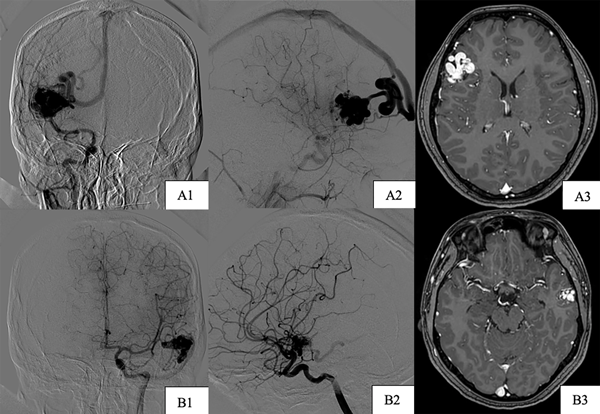

Paciente de sexo masculino, de 41 años de edad al cual se le diagnosticaron dos MAVs cerebrales de forma incidental, una supratentorial (temporal derecha), con aferencias de rama silviana y drenaje venoso precoz al seno sigmoideo homolateral y otra infratentorial (cerebelosa superior izquierda) con aferencias de la arteria cerebelosa superior homolateral y drenaje precoz hacia el seno sigmoideo homolateral, asociadas a la presencia de un aneurisma de bifurcación carotídea izquierda (Figura 2), dichas lesiones se identificaron en contexto de estudio del ROWS, con el cual había sido diagnosticado desde los 11 años.

Inicialmente se realiza la gradación del riesgo quirúrgico de la MAV supratentorial según la escala de Spetzler Martin, siendo de bajo grado por su tamaño menor a 3 cm, su localización en área no elocuente y su drenaje venoso superficial (Grado 1), por lo que se decide su exéresis mediante microcirugía y 2 meses después se realiza clipado microquirúrgico de la lesión aneurismática incidental.

Un año posterior al primer procedimiento se efectúa nueva angiografía digital que no evidencia remanentes de la MAV tratada y correcta exclusión aneurismática (Figura 3), sin cambios respecto al tamaño de la MAV cerebelosa izquierda. Se decidió realizar embolización de esta debido a la negativa del paciente ante una nueva propuesta quirúrgica, pero por el reducido calibre de la arteria aferente no fue posible, decidiéndose finalmente su tratamiento mediante radiocirugía.

Figura 2. Imágenes preoperatorias caso 1. A) MAV temporal derecha. A1) Incidencia frente aferencias. A2) Incidencia frente drenaje venoso. B) MAV cerebelosa superior izquierda. B1) Incidencia frente aferencias. B2) Incidencia frente drenaje venoso. C) Aneurisma de bifurcación carotídea izquierdo incidencia oblicua.

Figura 3. Imágenes postoperatorias caso 1, incidencias frente. A) Exéresis de MAV temporal derecha. B) Clipado de aneurisma de bifurcación carotídea izquierdo.